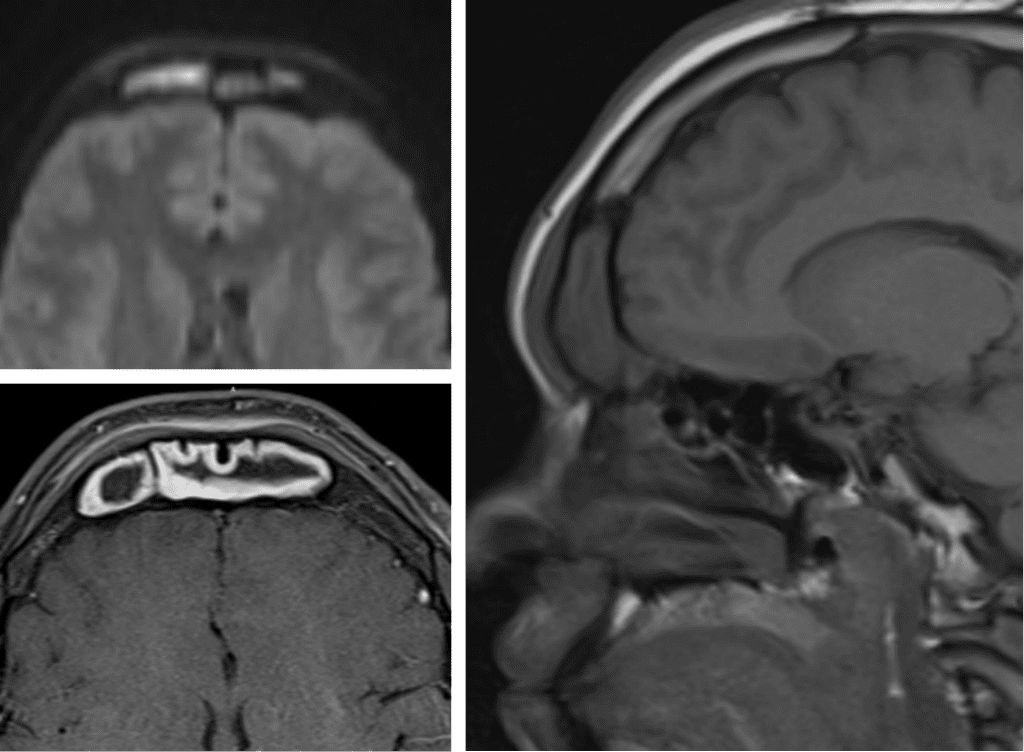

Pott’s Puffy Tumor

Subperiosteal abscess related to extension of acute frontal sinusitis through the calvarium.

Commonly associated intracranial extension needs to be evaluated with an MRI.

DWI sequence is key for abscess evaluation.